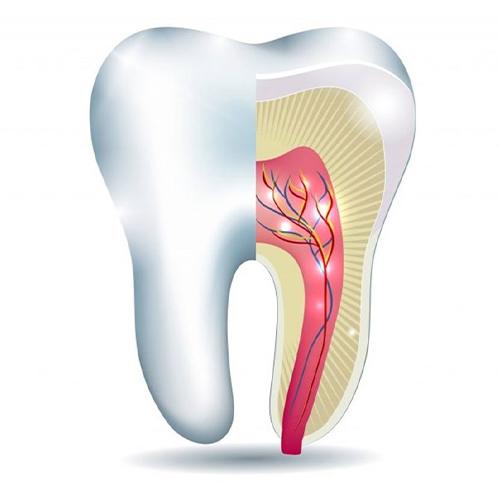

The outer portion or Crown of a tooth is a three-layered structure namely – Enamel, Dentin & Pulp. If the tooth decay is limited to the first two layers, it can be corrected with Filling/ Restoration. In case the tooth decay reaches the third layer and causes inflammation or infection of pulp, an RCT or Endodontic Treatment is needed.